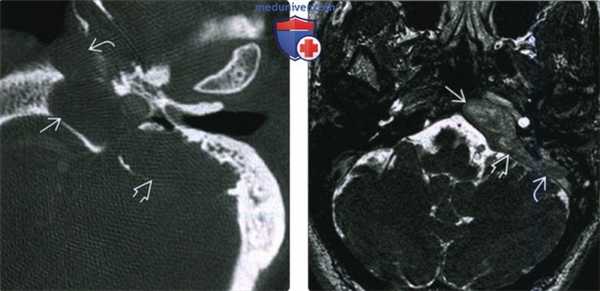

(Слева) При аксиальной КТ правой височной кости визуализируется врожденная холестеатома с ровными краями и интрамуральными включениями газа, приводящая к расширению вершины пирамиды. Холестеатома приводит к эрозии кост ного лабиринта внутреннего уха и дефекту кортикального слоя задне-медиальных отделов ВПВ.

(Справа) При аксиальной МРТ ДВИ у этого же пациента определяется гиперинтенсивный сигнал (рестрикция диффузии), характерный для врожденной холеаеатомы ВП.

(Слева) При аксиальной КТ в костном окне у пациента с парезом лицевого нерва определяется экспансивное поражение ямки коленчатого ганглия и лабиринтного сегмента канала ЧН. Врожденная холестеатома обусловливает ремоделирование костной ткани в медиальных отделах вершины пирамиды.

(Справа) При аксиальной МРТ Т2 ВИ у этого же пациента в ямке коленчатого ганглия и лабиринтном канале ЧН определяется врожденная холестеатома с гиперинтенсивным сигналом. Определяется также эрозия ВП и верхнего полукружного канала.